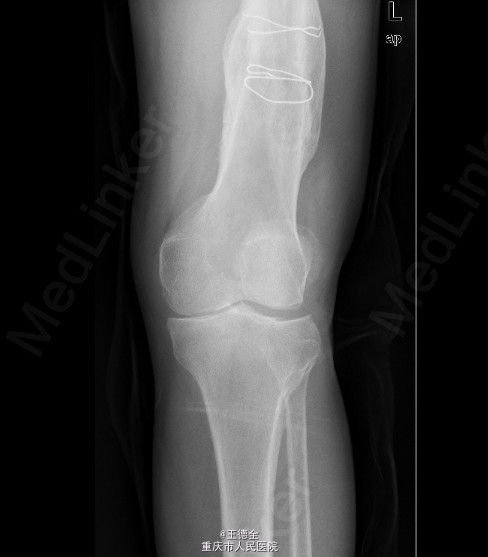

患者男,40岁,因“左股骨下段骨折术后4+年,左膝反复肿痛2年余”入院;自诉于4年前不慎被石块砸伤左大腿,伤后即觉左大腿疼痛,流血,左下肢活动障碍,患者伤后即到当地医院就诊,诊断为:"左股骨下段开放性骨折",予骨折切开复位内固定术,术后3个月下地行走,术后内固定螺钉松动、脱落,近两年来出现左膝关节肿胀、疼痛,活动时肿胀、疼痛症状加重,无畏寒发热、肢端麻木等,患者病后曾到当地医院就诊,予服药治疗后症状无明显好转,为进一步诊治遂来我院就诊,门诊拟"左膝骨性关节炎"收住我科,病程中,患者一般情况尚可,睡眠、饮食可,大小便正常,体重无明显改变。目前积极完善术前检查,拟做关节镜下关节清理术+左膝腘窝囊肿切除手术治疗。